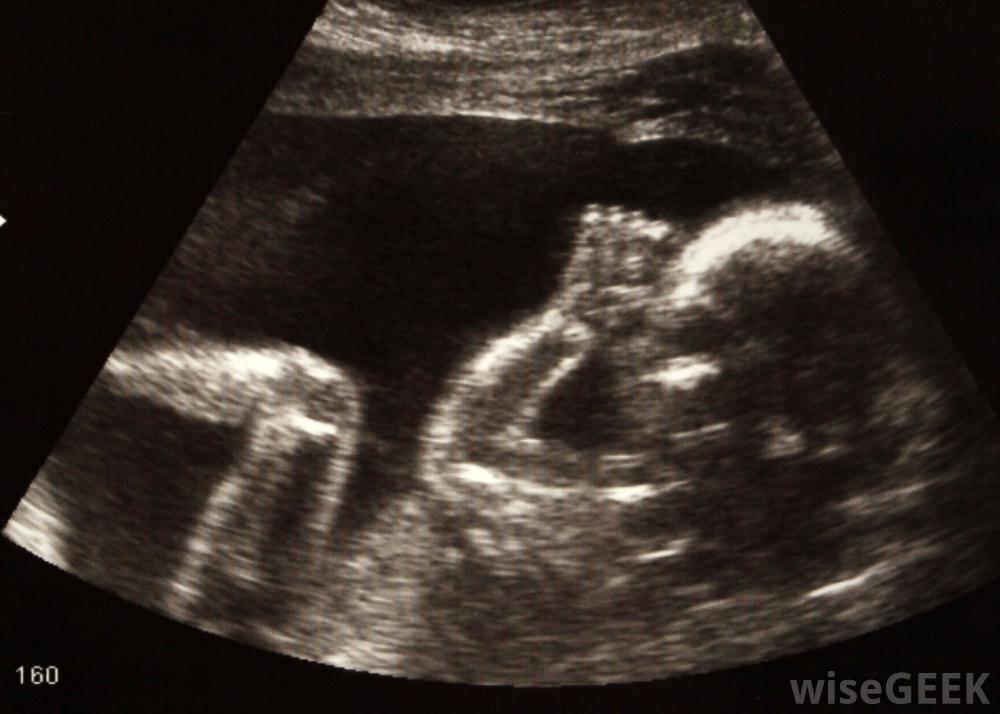

许多前置胎盘可以通过超声诊断怀孕时,前置胎盘有时会通过产前超声诊断出来,虽然这是一个值得注意的问题,但现在还不必担心,因为有时胎盘会生长到子宫上部,那里的血液供应更为充足,问题会自行解决然而,如果这种情况是在妊娠后半期被诊断出来的,它可能会引起关注。

有几个因素会增加前置胎盘的风险,例如双胞胎有时,医生会通过常规超声检查发现问题,有时,在准妈妈报告无痛出血或点状出血后才诊断出来。因为分娩时间很近,母亲和婴儿的风险会增加。妇女通常需要进行骨盆休息,这意味着不需要进行骨盆检查或性交,并且可以鼓励她们避免负重。如果突破性出血和前置胎盘持续到妊娠晚期,母亲可以卧床休息如果分娩时出现前置胎盘,大多数医生会建议剖腹产,这样可以安全地将一个或多个婴儿带出来,同时降低出血的风险。如果在怀孕的最后几周出现严重出血,即使宝宝会早产,也可能需要立即剖腹产,母亲可能会要求输血来补偿失血,产后还要进行监护,以确保出血完全停止有几个因素会增加前置胎盘的风险,包括年龄、吸烟、有过这种情况的病史、双胞胎和其他多胞胎以及以前的出生与其他妊娠并发症一样,这种并发症完全不受母亲的控制,尽管她可以减少一些危险因素,这就是为什么常规产前护理检查并发症和潜在的分娩问题如此重要